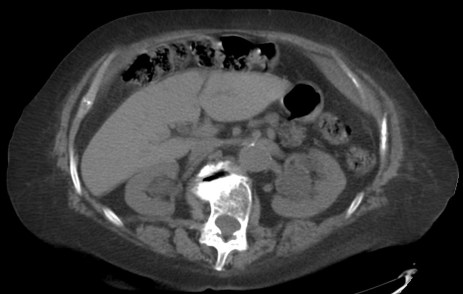

CASO: cáncer de mama. Control anual.

Hallazgos:

- Se observa un aumento de densidad con agrupación broncovascular que produce un borramiento del borde cardicaco derecho; hallazogos compatibles con atelectasia en el lóbulo medio. Véase el TC a continuación: